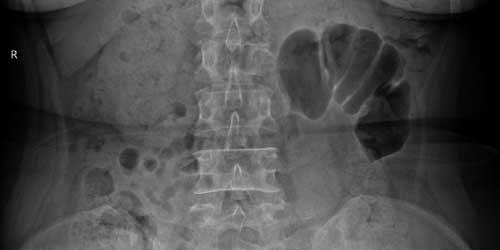

- Düz grafi: Düz radyografi, pediküllerin veya omur gövdesinin erozyonunu göstermek için kullanılır. Bununla birlikte, radyolojik bulgular sadece kemik yıkımı% 30-50'ye ulaştığında ortaya çıkmaktadır.